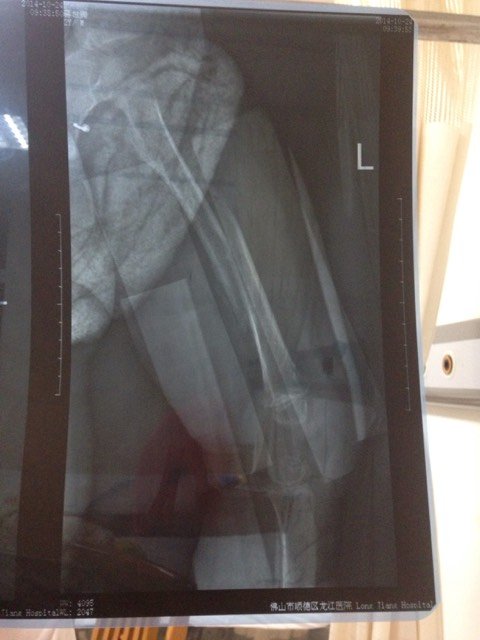

您好,我想请问一下,我家小宝,现龄1岁10个月,10月5号那天不小心滑倒在地上,导致左大腿骨骨断,现如今23天了,21号拍了片,看到骨头还没有对位,治疗方法是保守治疗,吊牵引!因为孩子太小,所以我们没有选择做手术!可是现在20多天过去了,骨头还没对位,我们大人心里很愁,请问医生,这到底是什么原因呢?是这里的医术不行还是本身的过程就是这样的呢?

您好,根据您的描述和提供的照片治疗,宝宝股骨中段骨折对位对线还是较差,以及保守治疗和牵引23天了,这种情况最好及时手术治疗更为妥当,宝宝小,虽然骨折对位的要求没有成人高,但是,照片上的情况确实相差较远,如果不及时手术的话,有可能影响宝宝今后的下肢功能,不可大意。